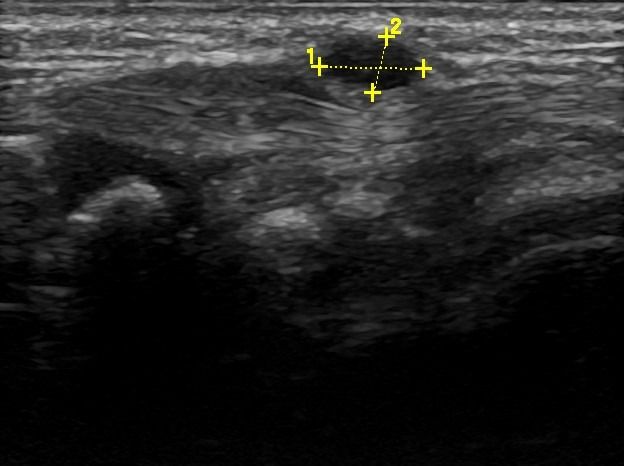

Hand Ultrasound examines joints, tendons, ligaments, nerves, and soft tissues of the hand. Pathologies that can be diagnosed by Hand Ultrasound are numerous, including:

Soft Tissue Pathologies

- Ganglia